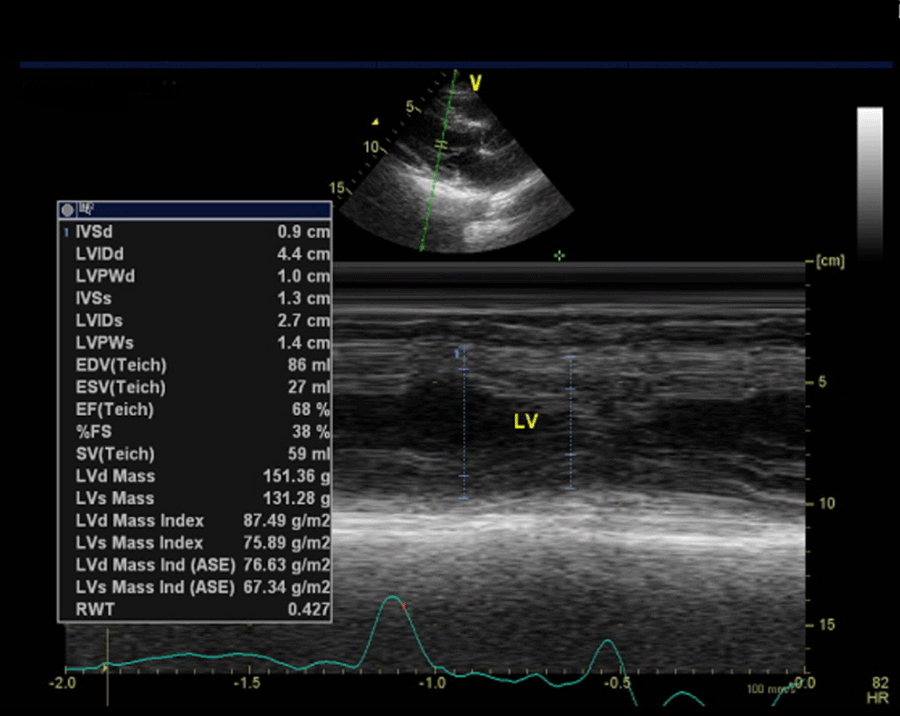

After three weeks of leaving the hospital, the patient was asked to undergo echocardiography. The results of this examination demonstrated that there was moderate mitral regurgitation with normal cardiac chamber dimensions. The left ventricular systolic function seemed normal with ejection fraction by Teich being 68%, as did the left ventricular diastolic function with E/A being 0.87 (Figure 7). On the other hand, the right ventricular systolic function appeared normal with tricuspid annular plane systolic excursion accounting for 1.8 cm.